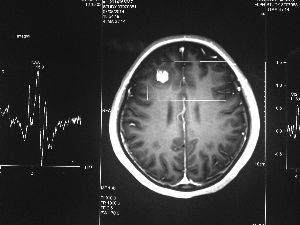

方框亮點(diǎn)為CT片顯示的異物

今年6月份,張敏在宿舍休息時(shí),又發(fā)起了癲癇,也是口吐白沫,渾身抽搐。送到蘇州一家大醫(yī)院,頭顱核磁共振檢查出,張敏大腦右額葉處有一處病灶,也就是大腦額頭處有個(gè)東西。

腦袋里的東西,到底是腫瘤還是其他什么東西,這個(gè)謎像個(gè)石頭一樣,壓得張敏一家人喘不過(guò)氣。7月份,張敏一家又來(lái)到南京腦科醫(yī)院求醫(yī),第三次檢查后,醫(yī)生覺(jué)得很像是寄生蟲。不過(guò),影像的檢查,只能作為醫(yī)生推測(cè)的依據(jù),具體是什么,只有手術(shù)拿出來(lái)后才能知道。